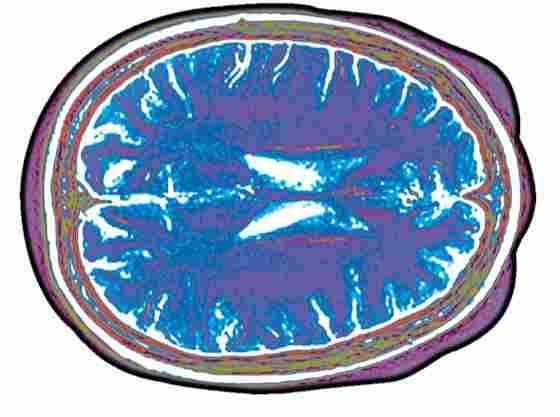

- Undergo a functional magnetic resonance imaging (fMRI)* while performing motor and memory tasks in the scanner